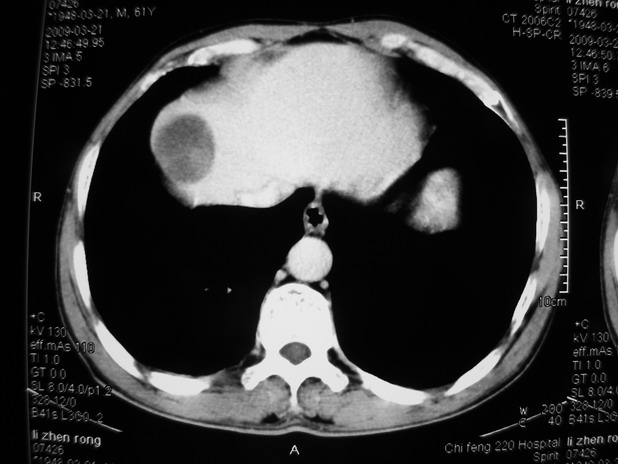

以下是引用余辉在2009-3-21 21:36:00的发言:[br]图像太乱了,建议楼主直接将强化数据按顺序列出来,病灶位置较表浅薄,有肝炎病史,灶内实性成分有显著强化,动脉期约60hu,考虑肝癌可能性大,进一步检查。